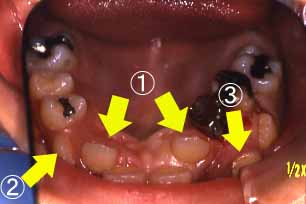

(2)反対咬合,低位咬合

正面

@上の左右の2番目の歯が反対咬合

(中に入っている)

A右上の犬歯(3番目の歯)が

頬より出てきました。

B左上4番目の歯が頬より出て

きました。

(455日目)

C右下4番目の歯がひっかか

っている。

D右下2番目の歯が外へ出て

いる。